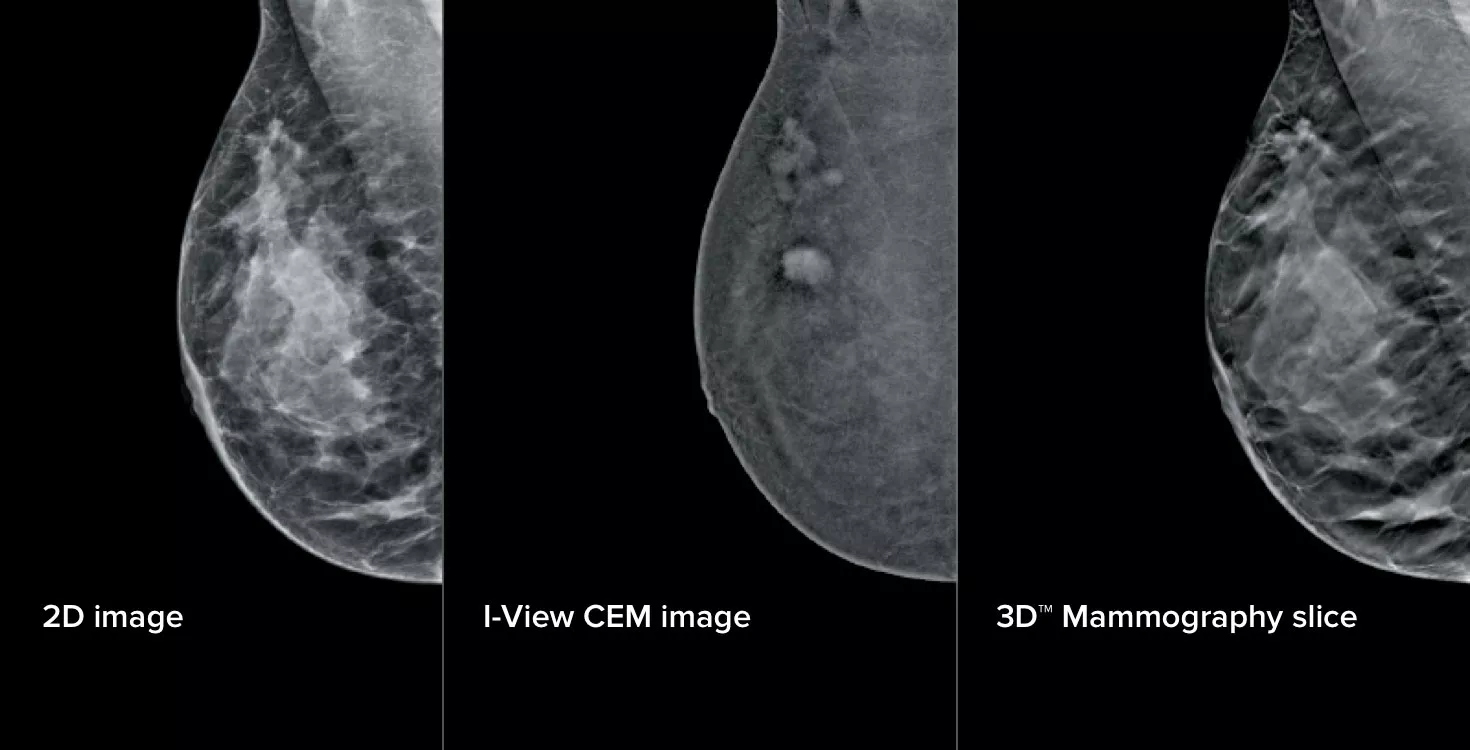

3 Images from 1 Compression

This software captures both anatomical and functional information in a single exam by leveraging our ability to provide 2D, contrast and tomosynthesis images in just one compression.1